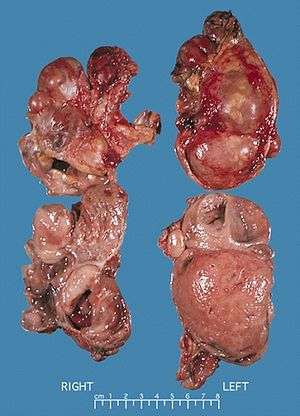

| Bilateral pheochromocytomas associated with Multiple endocrine neoplasia type 2 | |

Pheochromocytoma occurs in 33-50% of MEN2 cases.[3]

In a review of 85 patients 70 had Men2A and 15 had Men2B.[3] The initial manifestation of MEN2 was medullary thyroid carcinoma in 60% of patients, medullary thyroid carcinoma synchronous with pheochromocytoma in 34% and pheochromocytoma alone in 6%. 72% had bilateral pheochromocytomas.

Management of MEN2 patients includes thyroidectomy including cervical central and bilateral lymph nodes dissection for MTC, unilateral adrenalectomy for unilateral pheochromocytoma or bilateral adrenalectomy when both glands are involved and selective resection of pathologic parathyroid glands for primary hyperparathyroidism.